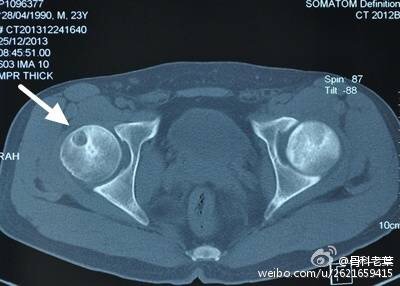

III期 磁共振出现异常,X线片显示软骨下塌陷(新月征),股骨头内出现空洞,股骨头没有变扁

II期和III期的患者治疗方法相同,因为此时股骨头虽然还没有变形,暂时还不需要行人工关节置换术,但是股骨头已经出现空洞,随时股骨头就会塌陷变形,所以单纯的股骨头减压术是不能达到治疗效果的。这时就需要在股骨头减压的同时,植入一根支撑棒,顶住股骨头空洞区,防止股骨头在负重的情况下过早塌陷。其他治疗同之前相同,口服以上药物,定期复查,密切观察病情发展,尽量避免重体力劳动和爬山爬楼。